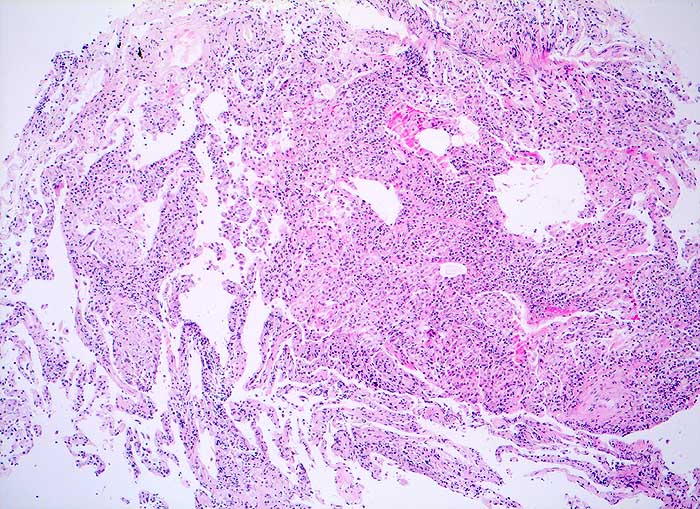

PathoPic – image database / PathoPic ID 5825 - Exogen allergisch Alveolitis

Exogen allergisch Alveolitis

Alveoläres Lungengewebe mit mässig bis deutlich ausgeprägter interstitieller Entzündung und einigen lockeren intraalveolären Granulomen. Herdförmige geringe interstitielle Fibrose. Geringe Alveolarzellretention.

Broncho-alveoläre Lavage: Massive Lymphozytose und deutliche Vermehrung der Alveolarmakrophagen mit schaumzelliger Umwandlung. Mässige Eosinophilie und deutliche Vermehrung der Mastzellen.

Die Vermehrung der Alveolarmakrophagen mit schaumzelliger Umwandlung in der BAL passt zu dem hier histologisch beobachteten Befund der Alveolarzellretention, was bei der exogen-allergischen Alveolitis häufig zu beobachten ist.